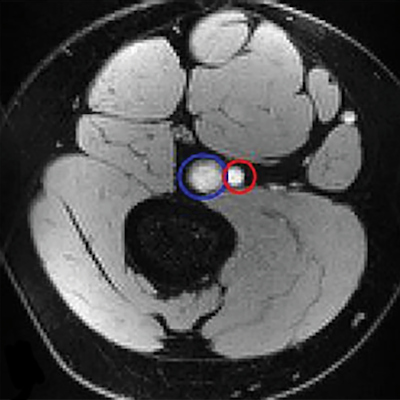

Grundinger and colleagues sought to better understand the "rewarding properties" of e-cigarettes and to compare their use to tobacco cigarettes via a study that explored the addictive potential of e-cigarettes and implications for smoking cessation. The study included 47 daily e-cigarette users -- 43 of whom were former tobacco smokers. Of the study participants, 32 used e-cigarettes exclusively, while 15 used both e-cigarettes and tobacco cigarettes; all underwent functional MRI. The investigators tracked each person's "anticipatory brain activation to reward-predictive stimuli for money, e-liquid, or tobacco cigarettes."

- Increased activation in the participants' limbic regions (i.e., the nucleus accumbens) prompted by anticipation of receiving e-liquid and money over tobacco cigarettes in exclusive e-cigarette users. The nucleus accumbens controls motivation and reward.